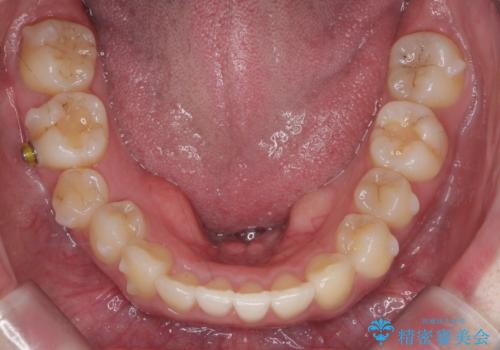

また、右下の奥歯に一部目立たないように部分的なワイヤー矯正を行い、右下の奥歯が反対咬合になっていたのもしっかり中に入れて治療しています。

奥歯の反対咬合を治すのはインビザラインではかなり難しいのですが、しっかり治療できました。